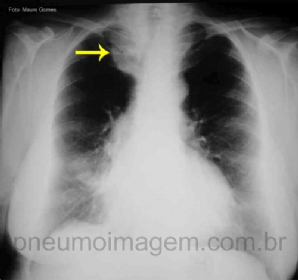

CASO CLÍNICO #39

O que as setas apontam nessa radiografia? Deixe os seus comentários abaixo! ***** What the arrows point in this chest X? Give your comments below!